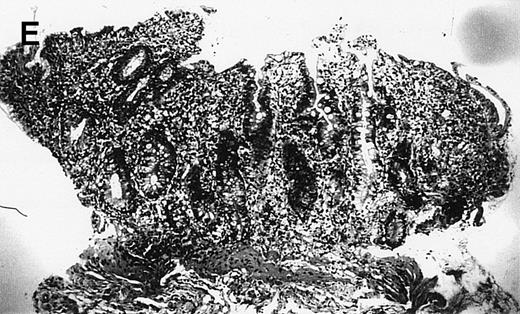

(A) Case no. 1. (B and C) Case no. 2. (D) Case no. 3. (E) Case no. 4. (A, B, D, and E) Duodenal biopsies showing total villous atrophy with crypt hyperplasia and infiltration of lamina propria by nonatypical inflammatory cells (Hematoxylinandeosin; original magnification × 10). (C) Jejunal biopsy showing villous atrophy and ulcerations with regenerative epithelial changes on the border of ulcerations; no evidence of lymphoma.

The 4 patients with complicated CD had duodenal biopsies consistent with untreated CD; total villous atrophy, intraepithelial lymphocytosis, crypt hypertrophy, and inflammation of lamina propria with benign-appearing lymphocytes, plasma cells, and eosinophils were observed. There was no histological evidence of lymphoma. Patient no. 4 also had biopsies performed at the border of duodenal ulcerations that showed epithelial erosions without histological evidence of lymphoma.